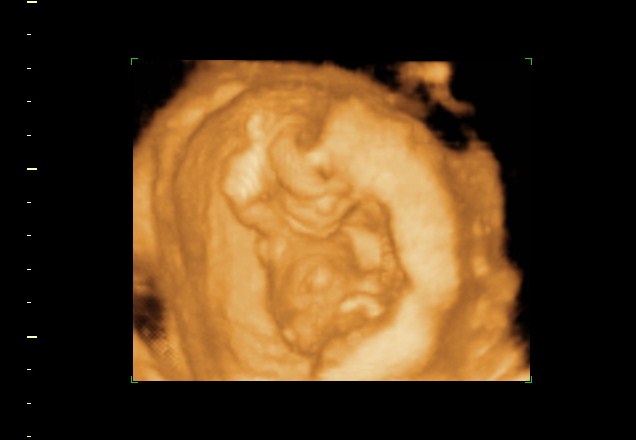

These pictures were from my 14week 1 day ultrasound. Boy or girl?! Help me out :crawl:

No idea what I'm looking at, but my doctor says 14 weeks was too early to tell with a potty shot? He always made me wait until at least 16.

Early but looks boy to me. Girls at 14 weeks, if they still have anything between the legs, is usually short and very pointy. I think this is a boy.